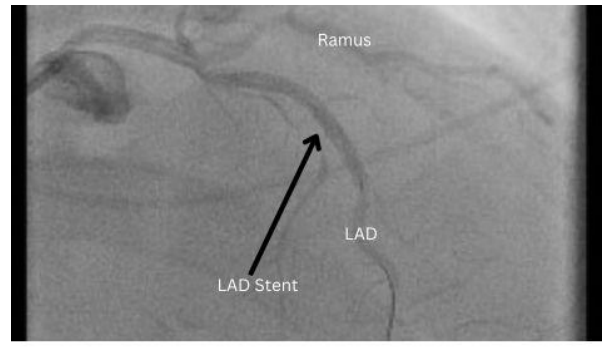

He successfully underwent a percutaneous transluminal coronary angioplasty (PTCA) with two DES placements in the mid-LAD and the mid ramus intermedius (Figure 2 and Figure 3) with post-procedure initiation of 90mg Ticagrelor and Aspirin along with guideline-directed medical therapy.

Figure 2: Angiographic image of the stented LAD